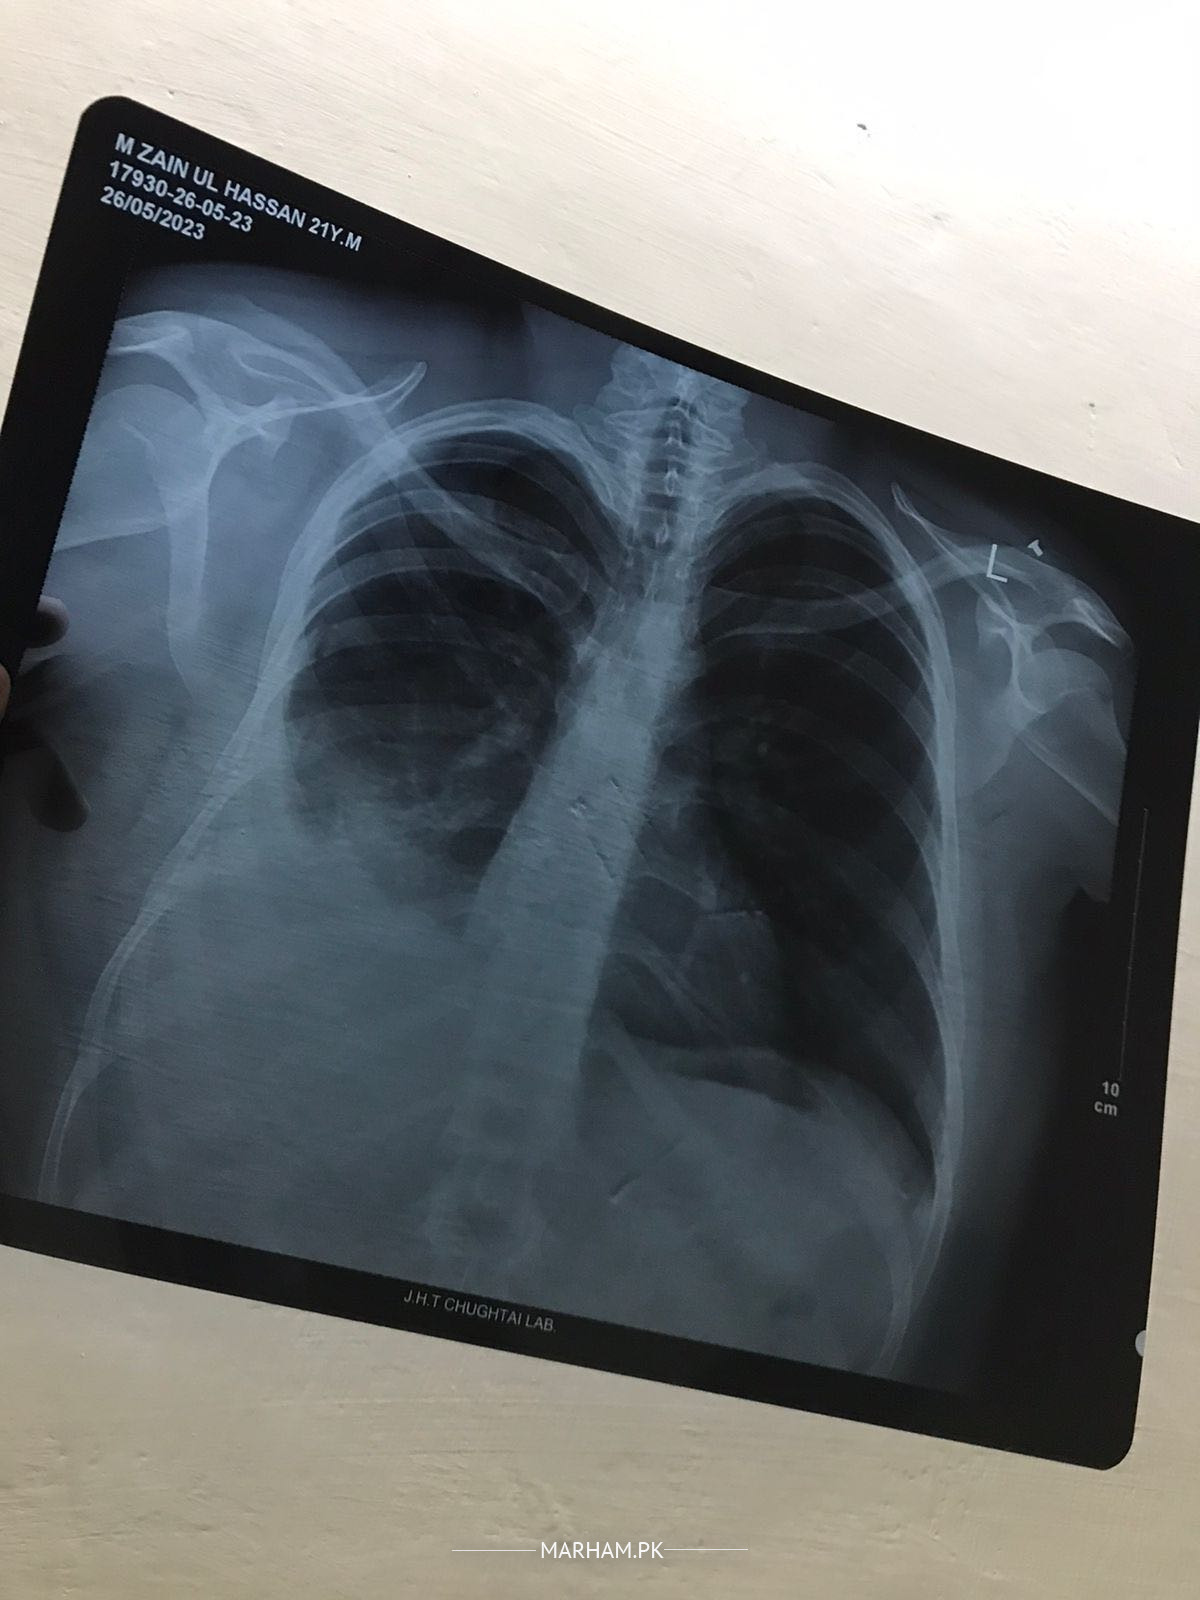

My brother has an accident 2 months before . He fell on his chest . He was feeling ok so we didn’t had an x ray. A week before he started having symptoms chest and back pain, dry cough, difficult laboured breathing, fever, and loss in weight. Someone is saying its TB , others say the you should go for lung tapping and some say about the lung surgery . Kindly guide me in this difficult situation when we can’t decide anything

plural tap and send fluid for cytology examination to confirm diagnosis

yes plz go for pleural tap and cytology

diagnosis will be confirmed after that

go for plural tap and send fluid for cytology diagnosis.